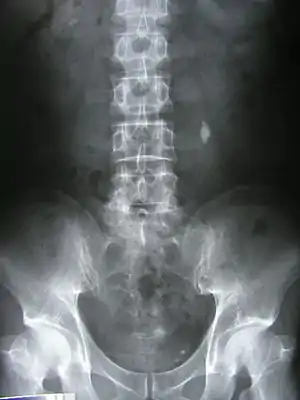

![]() Рентгенограма, на якій видно камінь (конкремент) у лівому сечоводі Рентгенограма, на якій видно камінь (конкремент) у лівому сечоводі | |